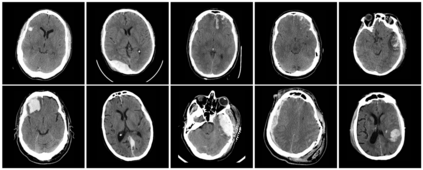

Machine learning models are becoming commonplace in the domain of medical imaging, and with these methods comes an ever-increasing need for more data. However, to preserve patient anonymity it is frequently impractical or prohibited to transfer protected health information (PHI) between institutions. Additionally, due to the nature of some studies, there may not be a large public dataset available on which to train models. To address this conundrum, we analyze the efficacy of transferring the model itself in lieu of data between different sites. By doing so we accomplish two goals: 1) the model gains access to training on a larger dataset that it could not normally obtain and 2) the model better generalizes, having trained on data from separate locations. In this paper, we implement multi-site learning with disparate datasets from the National Institutes of Health (NIH) and Vanderbilt University Medical Center (VUMC) without compromising PHI. Three neural networks are trained to convergence on a computed tomography (CT) brain hematoma segmentation task: one only with NIH data,one only with VUMC data, and one multi-site model alternating between NIH and VUMC data. Resultant lesion masks with the multi-site model attain an average Dice similarity coefficient of 0.64 and the automatically segmented hematoma volumes correlate to those done manually with a Pearson correlation coefficient of 0.87,corresponding to an 8% and 5% improvement, respectively, over the single-site model counterparts.